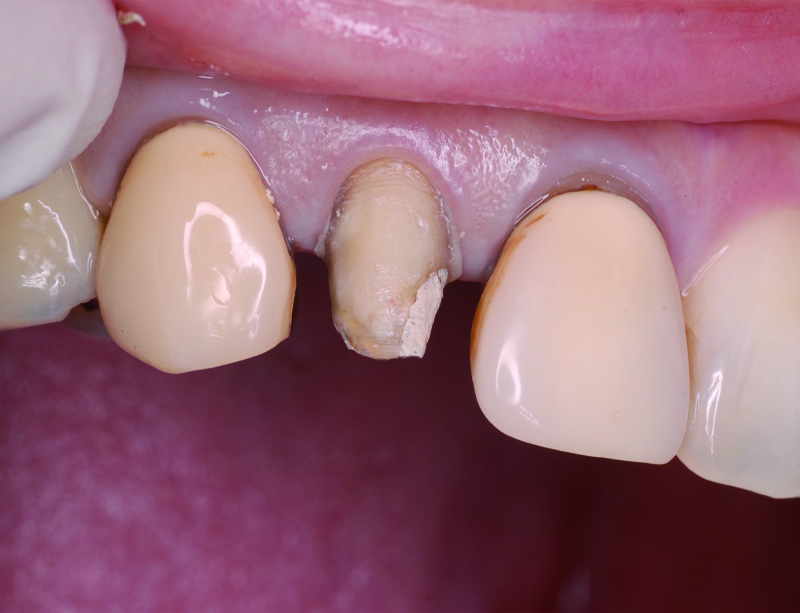

術前の状態です。右上中切歯の被せ物が合っていないことがわかります。また周りの歯の樹脂も劣化が認められます。

被せ物を外すとう蝕が認められました。

土台外すとさらに根管の中にもう蝕が認められました。

残っている歯の量が少ないため、根管治療後に部分矯正にて歯を引っ張り上げる(矯正的挺出)こととしました。

その際は表には仮歯をつけて見た目の確保を行います。

矯正的挺出が終わった状態です。歯とともに歯肉と骨も一緒に引っ張り上げられるので、

手術(歯冠長延長術)によって歯肉と骨を整形し、健康な歯の量を確保します。

歯冠長延長術を行ったところです。

その後土台を築造し、型取りを行います。

右上中切歯にセラミッククラウンを装着して、周りの歯の樹脂もやり替えを行いました。